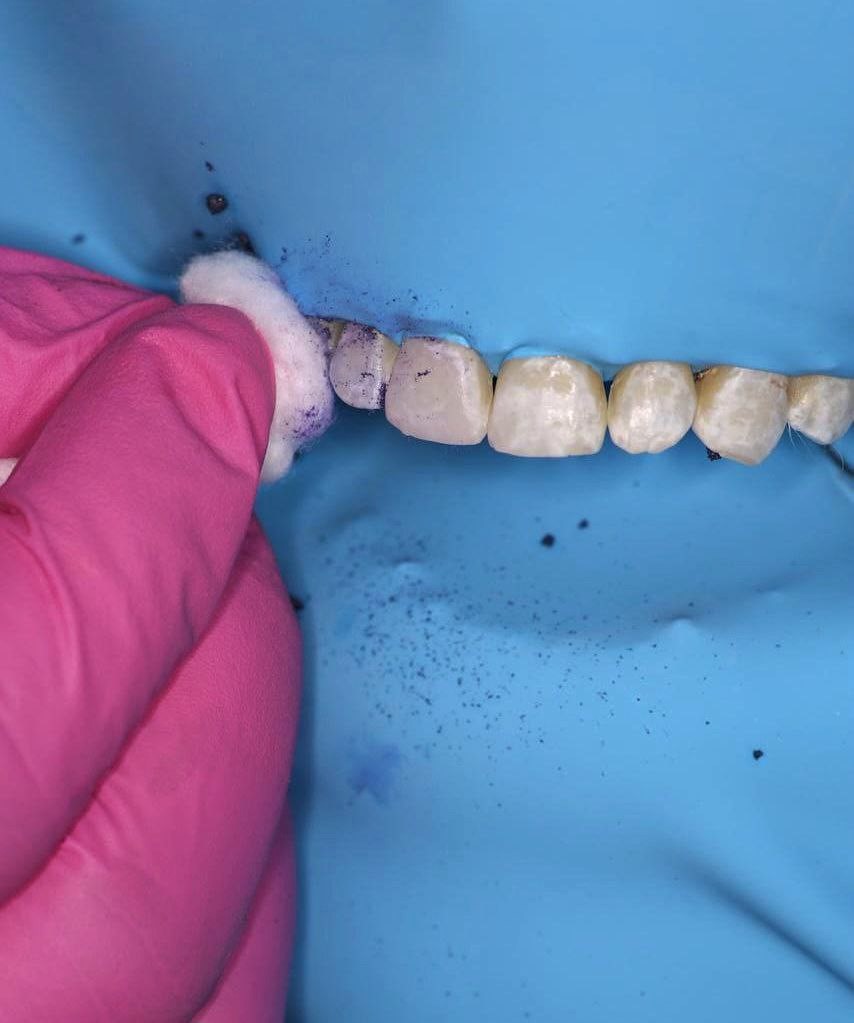

Tras ejecución del aislamiento absoluto del campo operatorio y profilaxis con piedra pómez el material de microabrasión Opalustre fue colocado sobre el esmalte de las caras vestibulares de los dientes anteriores, tras espera de un minuto aguardando se produzca la erosión, a través de una presión suave con puntas de goma suaves (OpalCups) mediante contraángulo durante un minuto el material fue distribuido uniformemente sobre las superficies (figura 2).

Figura 2. Colocación el material de microabrasión Opalustre sobre el esmalte en las caras vestibulares de los dientes anterosuperiores